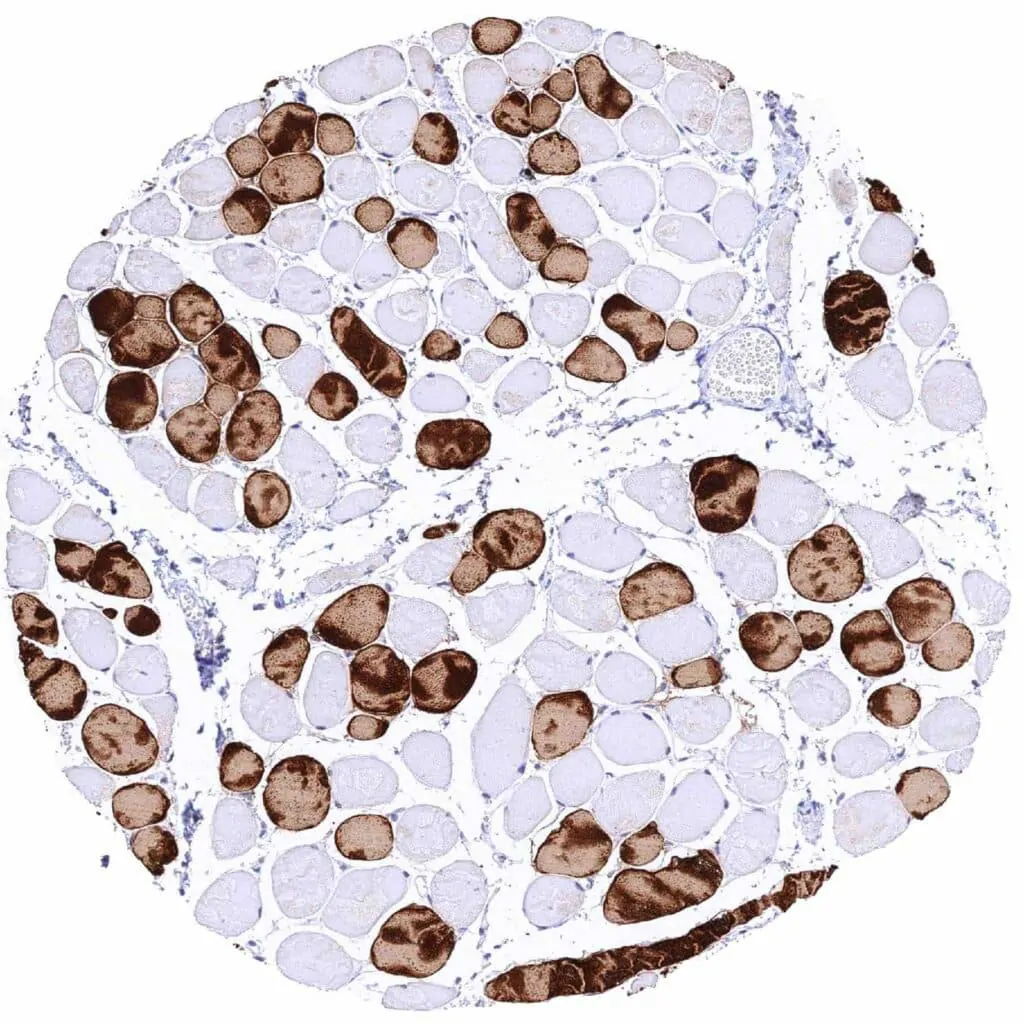

Skeletal muscle – Strong cytoplasmic MYH7 staining of a subset of muscular cells

Skeletal muscle – Strong cytoplasmic MYH7 staining of about half of muscular cells

Skeletal muscle – Strong cytoplasmic MYH7 staining of most muscular cells

Skeletal muscle – Variable intensity cytoplasmic MYH7 staining of a subset of muscular cells